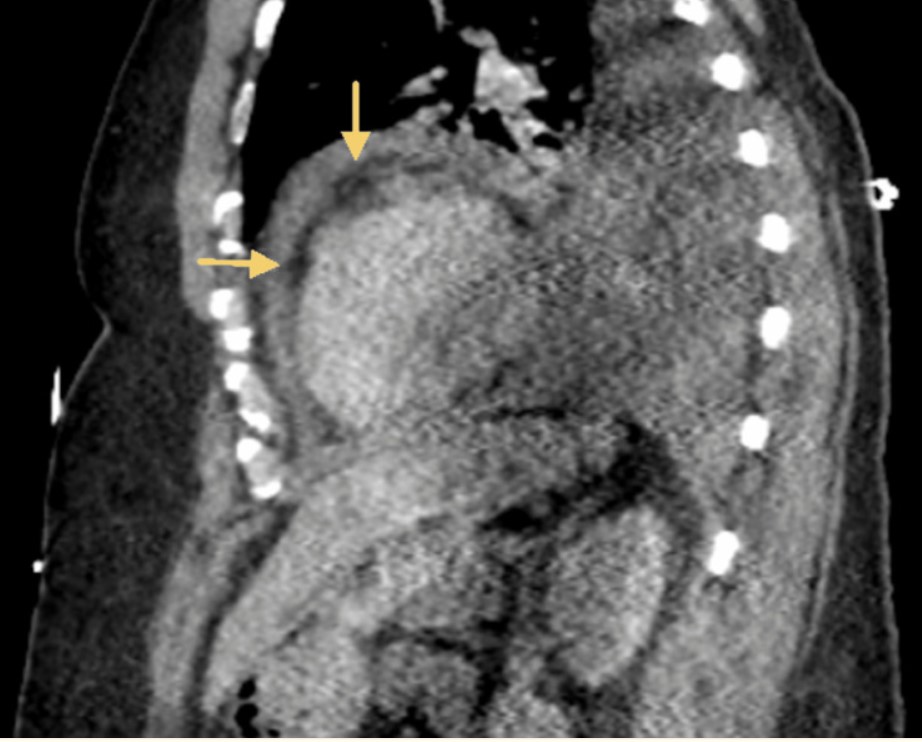

Dans ce rapport de cas, les soins anesthésiques pour un patient suspecté de péricardite/myocardite induite par la vaccination COVID-19 pendant la chirurgie de la fenêtre péricardique sont présentés.

Après la vaccination contre la COVID-19, les patients peuvent présenter des symptômes cliniques et des signes de péricardite et de myocardite, notamment des douleurs thoraciques, un essoufflement, de la fièvre et des malaises. Des niveaux élevés d’enzymes cardiaques telles que la troponine et la créatine kinase-MB peuvent être détectés par des tests de laboratoire.

Une échocardiographie transœsophagienne (ETO) est un type particulier d’échocardiogramme. Ce test est habituellement effectué lorsque le médecin veut examiner de plus près le cœur afin de savoir s’il produit des caillots sanguins. Ellle doit être systématique

L’ETO doit être considérée comme une technique de routine afin de minimiser les interventions chirurgicales inutiles et le risque de dégénérescence myocardique. Pour fournir à ces patients le meilleur traitement possible, les cliniciens, les éducateurs et les chercheurs doivent être conscients de ces problèmes potentiels et collaborer étroitement avec l’équipe multidisciplinaire.